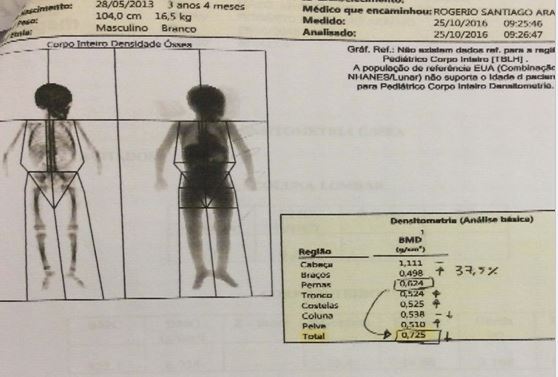

Primeira densidometria óssea (DO1) foi realizada antes do primeiro ciclo com pamidronato dissódico, evidenciando densidade mineral óssea (DMO) de corpo inteiro de 0,949 g/cm², DMO da coluna lombar (vértebras L1-L4) de 0,410 g/cm³ e 26,2% de massa gorda. Após primeiro ciclo do tratamento, segunda DO (DO2) realizada evidenciou DMO de corpo inteiro de 0,725 g/cm², DMO da coluna lombar de 0,460 g/cm² e 13,4% de massa gorda. Após terceiro ciclo com pamidronato dissódico, terceira DO (DO3) mostrou DMO de corpo inteiro de 0,708 g/cm², DMO da coluna lombar 0,547 g/m² e 23,4% de massa gorda. A quarta DO4 (imagem 5) mostrou DMO total de 0,727 g/cm2, DMO(L1-L4) de 0,614 g/cm² e 25,2% de massa gorda.

Após tratamento com ciclos de pamidronato dissódico, que é um potente inibidor da reabsorção óssea mediada por osteoclasto – inibe o acesso de precursores osteoclásticos para o tecido ósseo e sua subseqüente transformação em osteoclastos maduros com atividade de reabsorção óssea, a cada quatro meses, foi possível perceber significativa melhora da densidade mineral óssea (DMO), demonstrada pelo aumento de 35% de massa óssea dos membros superiores (não sendo possível a comparação com MMII visto que o mesmo encontrava-se imobilizado devido a fraturas na realização da DMO antes do ciclo).

O paciente iniciou o tratamento descrito com 2 anos e 6 meses, sendo portanto, um caso relevante devido à escassez, na literatura, de trabalhos acerca do uso de pamidronato dissódico em paciente menores de 3 anos. Também é relevante evidenciar a eficácia terapêutica comprovada após o tratamento, através da evolução dos resultados da DMO apresentadas na tabela 1.